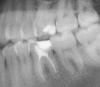

Наконец решил заняться зубами, т.к. стоматологов побаиваюсь, обращался редко. Сейчас мне 28 лет, три мертрых 6-ки, нервы были удалены более 6-8 лет назад. Хочу не спеша и спокойно привести зубы в хорошее состояние, чтобы они мне прослужили максимально долго, чтобы я все-таки не потерял их и в старости не думал про имплантацию. Конкретно сейчас интересует нижняя левая шестерка, вот она:

Изначально поводом послужило то, что пломба отходит спереди, и туда попадает пища, и в зубе, под пломбой, скорей всего, уже образовался серьезный очаг кариеса. Думал поставить пломбу, но специалсты говорят, что уже надо коронку. Какие вы посоветуете варианты? Эстетически мне все-равно, как он будет выглядеть. Главное, подчеркиваю - надежность, долговечность.

Перелечить-и вкладки, коронки. Седьмые нижние тоже требуют внимания: кариес. На 26 пломбу нужно менять. На 27, скорее всего, кариес на передней контактной пов-ти.